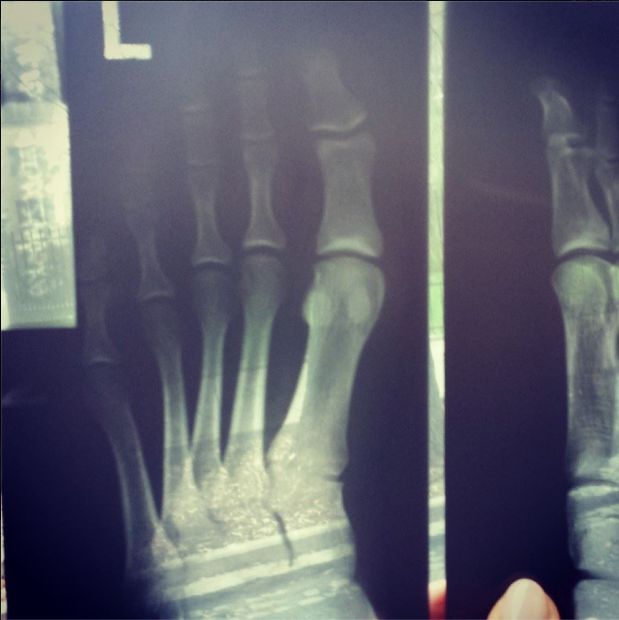

Aktorka miała ostatnio wypadek na planie Na Wspólnej. Na swoim Facebooku pochwaliła się zdjęciem rentgenowskim. Na szczęście nie wykryto złamań (oryginalna pisownia):

Poznajcie moje wnętrze Zlamania brak. Uff… mocno dokuczające stluczenie. Palec podwoil swoja objętość i przybrał sliwkowy kolor… a to wszystko to nie skutek ekstremalnego treningu a sceny na planie “Na Wspólnej”. To się nazywa poświęcenie dla roli.